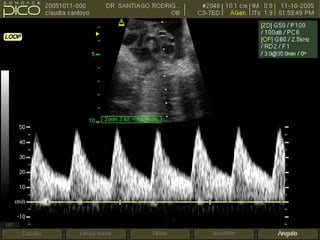

FLUJOMETRIA NORMAL A LA SEMANA 7 A 10-13

PICO SISTOLICO

VELOCIDAD DE FIN DE DIASTOLE

IR: MENOR DE 0.7

S/D MENOR DE 3.5

FLUJOMETRIA NORMAL ALA SEMANA 7 A 10-13

ANORMALIDADES DEL CORDONUMBILICAL (NUDO) PICO SISTOLICO VELOCIDAD DE FIN DE DIASTOLE

IR: MENOR DE0.7 S/D MENOR DE 3.5